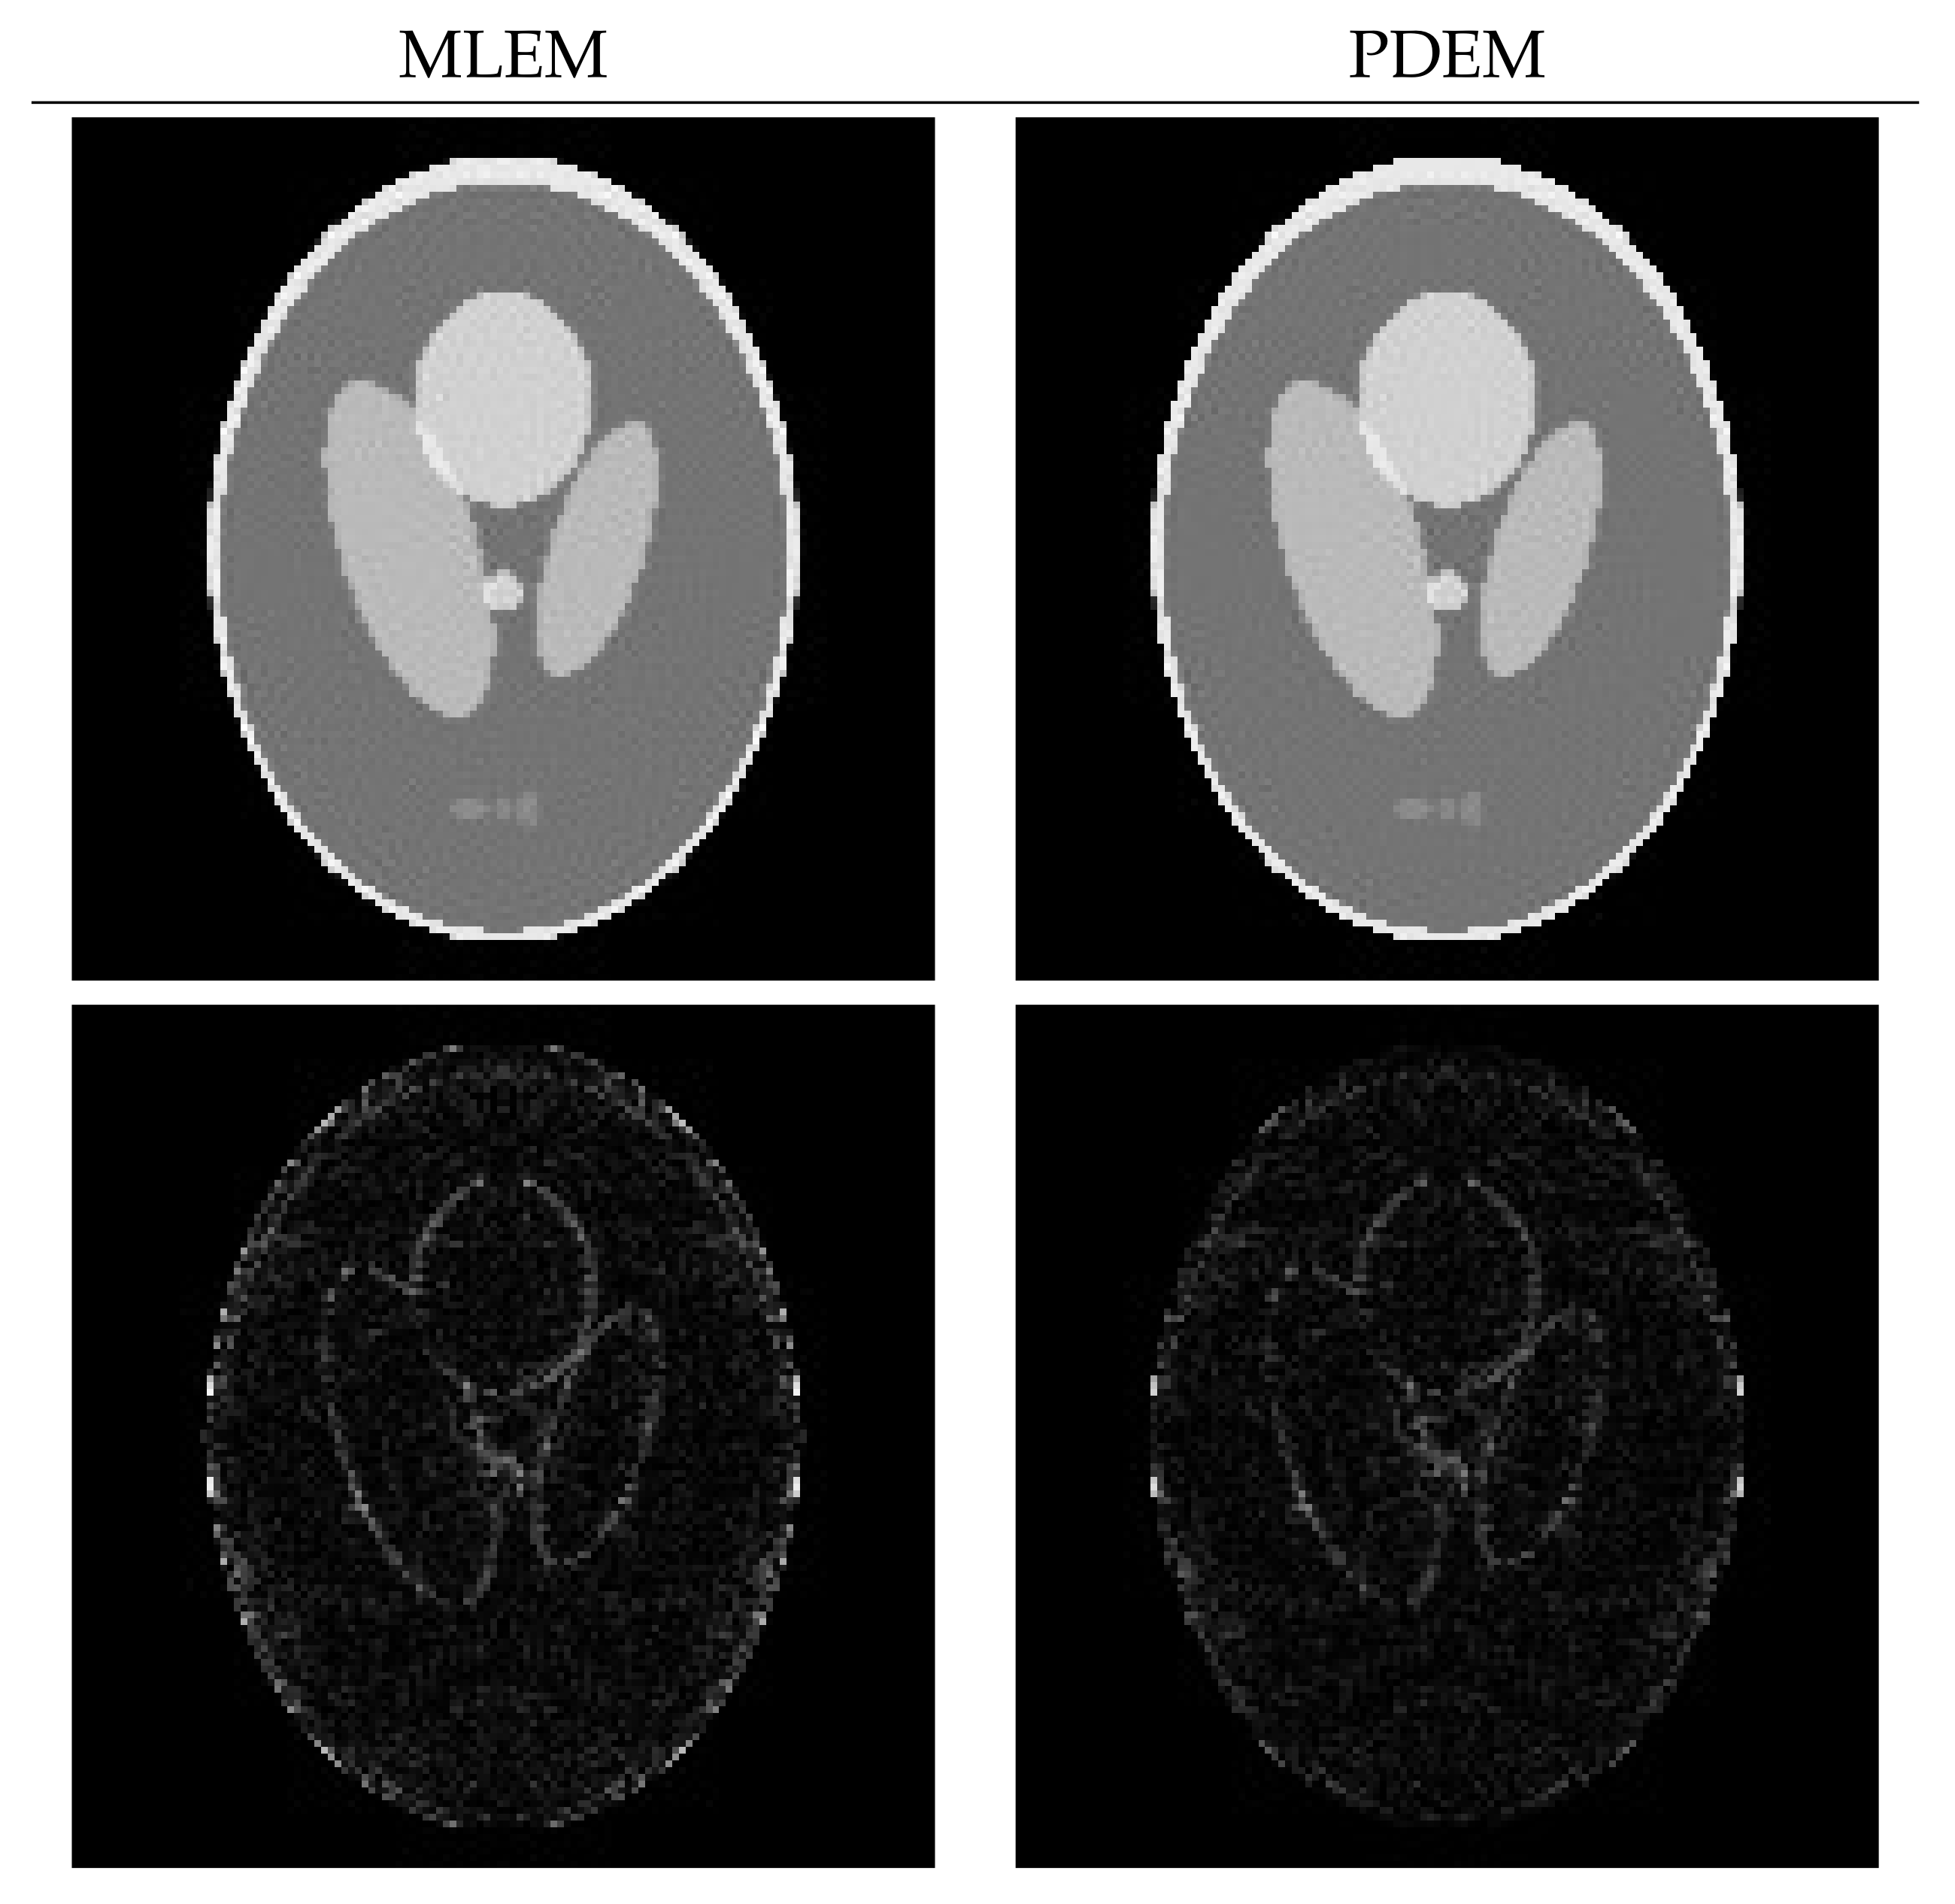

4.2. Reconstruction Using Physical Phantom